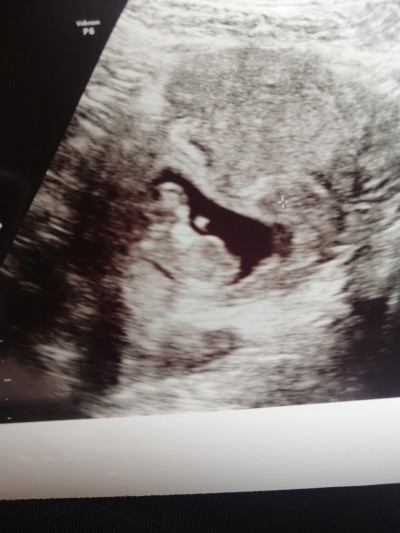

Bu post eda güneş için açılmıştır cinsiyet tahmini :D

Askom bas bas bagriyo erkegim ben diye :DD

Bnanane ben pipi isterim göster

Hahahaha benimkinin pipisi kısa bacım :D

Cınsıyet bılıncısımısınnnnn kız seen